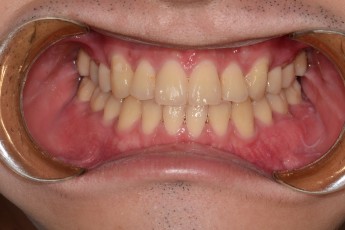

Before

After